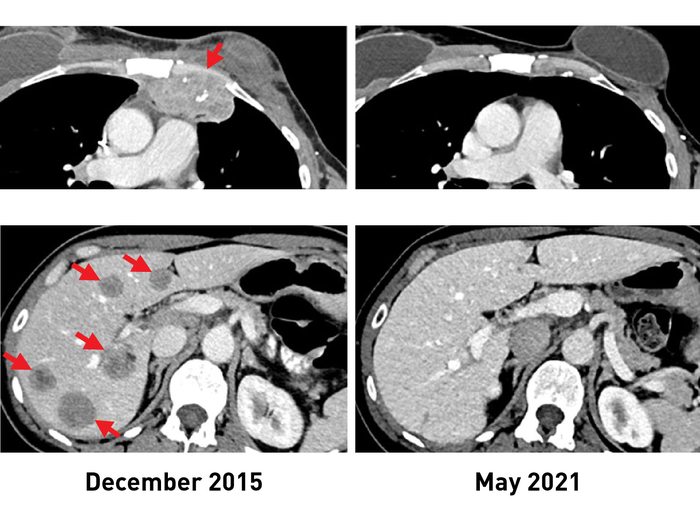

After the treatment, tumors shrank in three of the six women. One is the original woman reported in the 2018 study, who remains cancer free to this day. The other two women had tumor shrinkage of 52% and 69% after six months and 10 months, respectively. However, some disease returned and was surgically removed. Those women now have no evidence of cancer approximately five years and 3.5 years, respectively, after their TIL treatment.